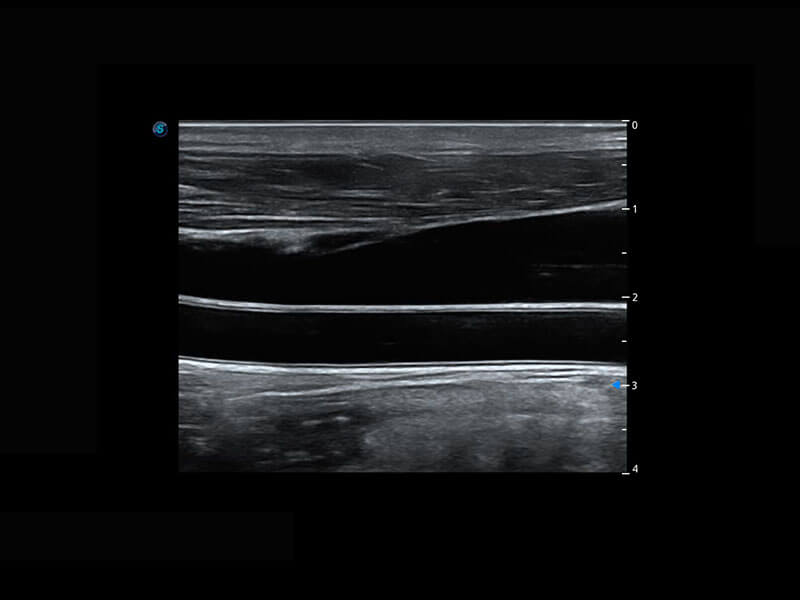

乳腺超声 / 新生儿

P60搭载宽频带线阵探头、宽景成像、弹性成像技术,为您提供乳腺全面应用方案。P60支持高频相控阵探头、线阵探头、腹部高频探头、腹部微凸探头等,丰富的探头群搭载敏感的彩色血流成像,适用于新生儿多种脏器检测要求,满足新生儿筛查需求。

• 乳腺导管癌

• 乳腺癌显微血流

• 新生儿肝血管癌

• 新生儿脊髓圆锥

• 新生儿心脏